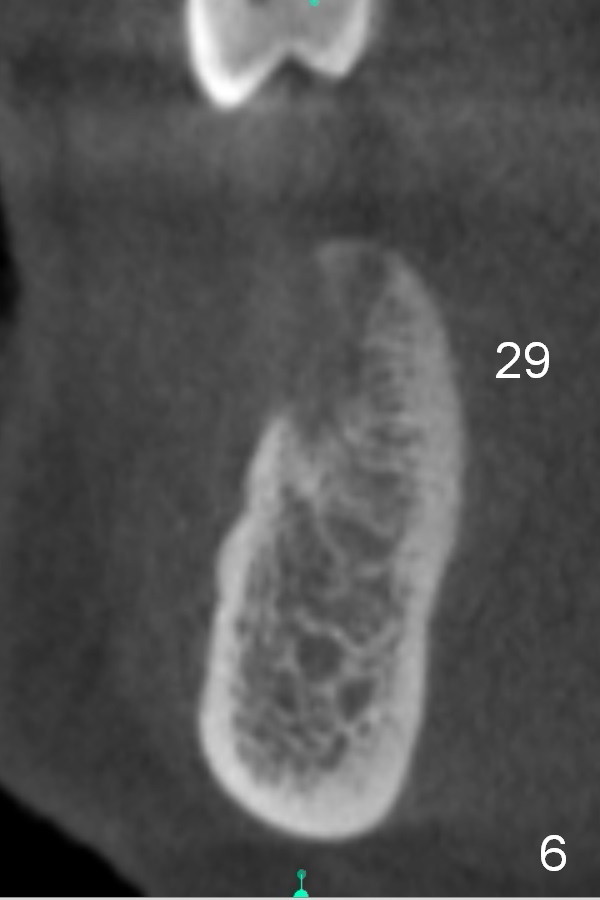

Chief complaint of a 69-year-old lady is "I cannot eat after bottom right bridge removal" (Fig.1). Exam reveals that the tooth #15 is also missing (Fig.2). Four implants are planned. CBCT shows low density of #31 socket (Fig.3,4, bone expanders) and the buccal coronal portion of the #29 socket (Fig.3,6,7, place implant as lingual as possible). The alveolus at the site of #30 is atrophic coronally (Fig.5). If insertion torque of individual implants is reasonably high, an immediate provisional bridge will be fabricated.